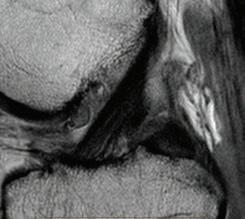

Perth Radiological Clinic’s MSK sub-specialist team

At Perth Radiological Clinic your musculosketal (MSK) investigations are reported locally by Perth’s largest team of musculoskeletal and spinal radiology experts.

• Rapid access to high quality scans and image guided injections.

• MRI appointments available evenings and weekends.

• Fast report turnaround times delivered by Perth’s largest team of musculoskeletal and spinal radiology experts.

• Radiologists available to discuss the imaging and interventional requirements

PRC MSK sub-specialist, Dr Matt Prentice saysOur rapid turnaround reports expedite the path to appropriate treatment, can rule out serious pathology or help differentiate acute injury from chronic non traumatic conditions.

Please contact your customer relations team for more information or email assist@perthradclinic.com.au